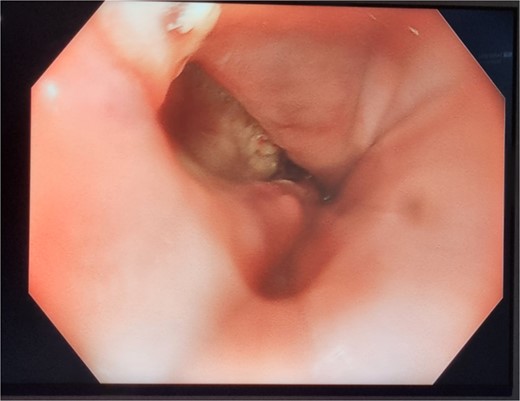

Unfortunately, the patient developed respiratory sepsis and a small bowel obstruction, requiring ICU readmission and intubation. An exploratory laparotomy on postoperative day 5 showed no evidence of ischemia or perforation. A subsequent OGD on postoperative day 8 revealed a 20% staple line defect (Fig. 4a), leading to VACStent and right chest drain insertion.

Patient Four: (a) Before VACStent insertion, showing the oesophageal defect. (b) After VACStent treatment, demonstrating successful defect closure.

Following the removal of the VACStent on postoperative day 13 (Fig. 4b), the patient underwent a prolonged antibiotic course and received dietician support for jejunal feedings. Despite complications, including unsuccessful extubation and bilateral pleural effusions, the patient gradually improved with comprehensive care. A drain was placed on postoperative day 23 to address chest wall collections, and the patient was weaned off the tracheostomy by day 31. The patient continued to recover, managed hypertension, and was discharged home on day 82, with various supports in place and a follow-up scheduled in the clinic.